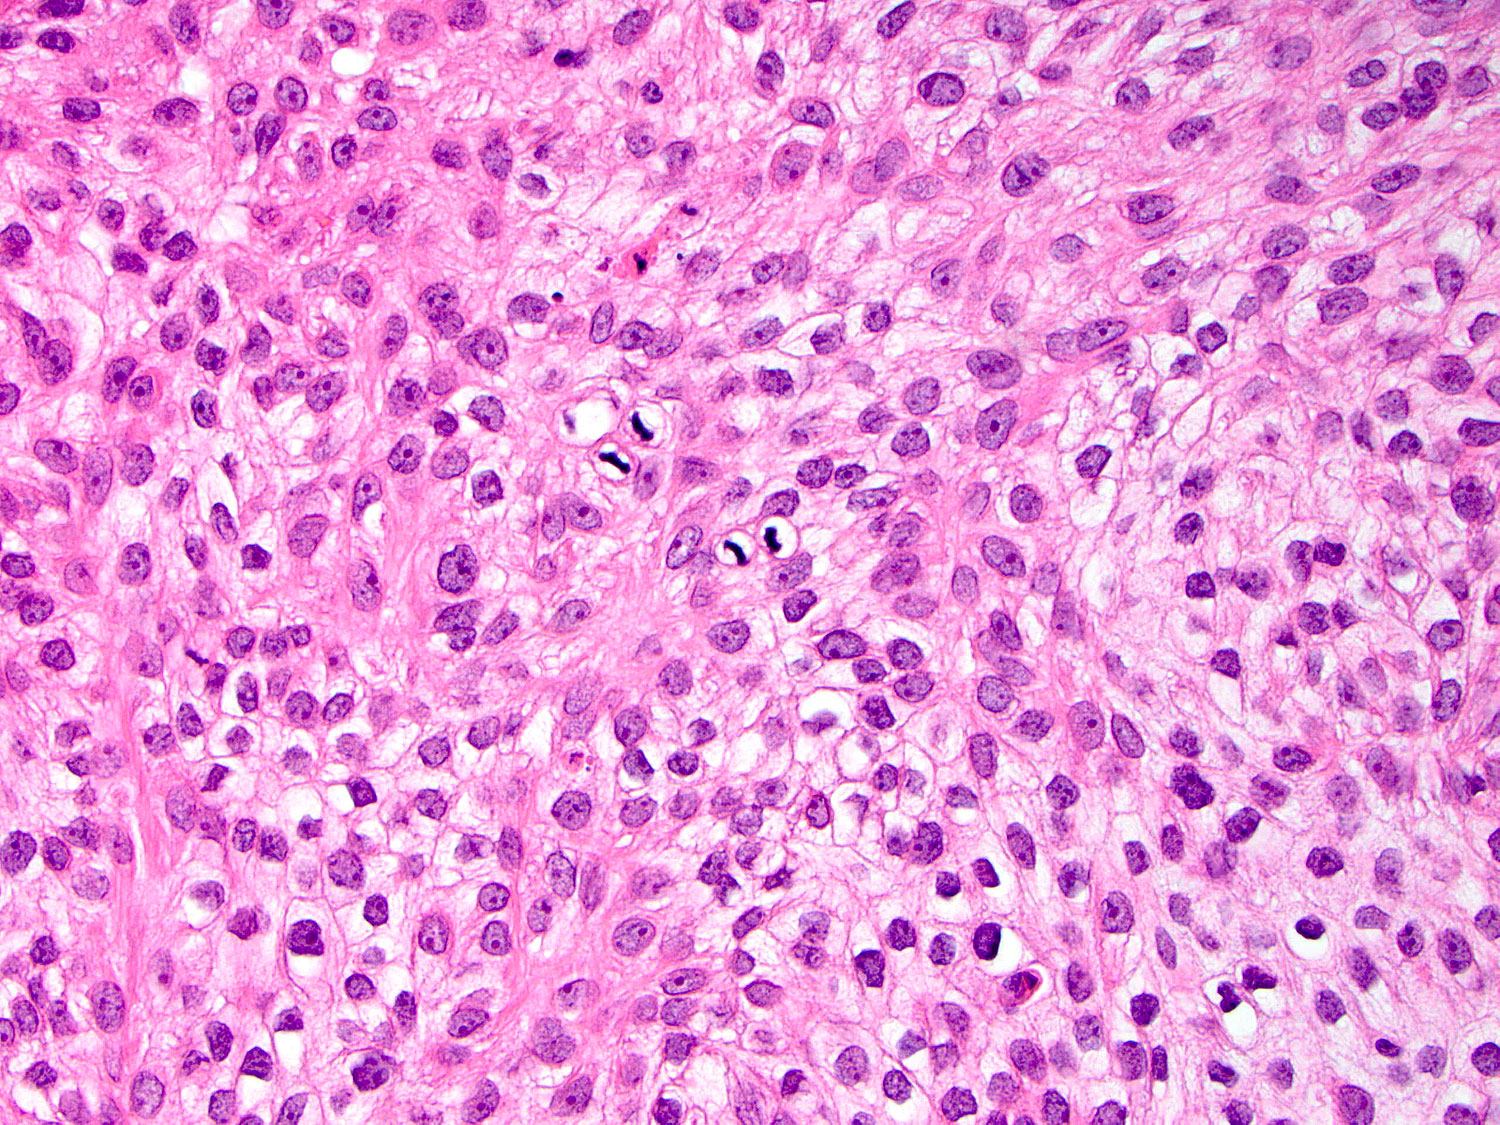

H&E staining (40x objective)